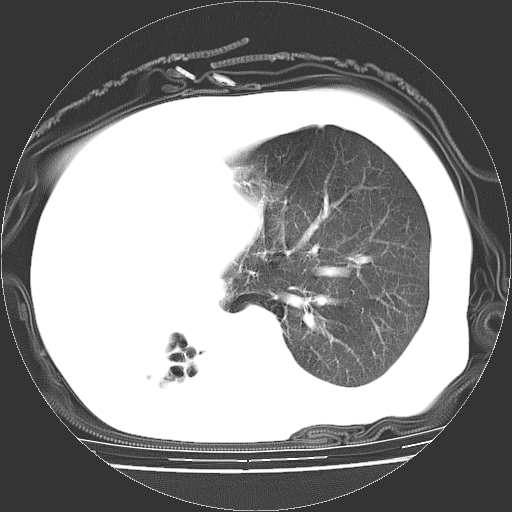

标题: CT23991:女,72岁,咳嗽、憋气一周。 [打印本页]

女,72岁,咳嗽、憋气一周,十年前曾患肺结核及胸膜结核。

右侧毁损肺,右侧纵隔疝

右侧毁损肺,右侧纵隔疝,左肺代偿!

1.右侧损毁肺伴胸膜钙化,2.左肺小结节灶,良性可能大,注意复查。3.肝脏左叶囊肿。4.先天性一侧肺不发育待出外(右侧胸廓无明显塌陷)。对比原片应该非常有帮助。